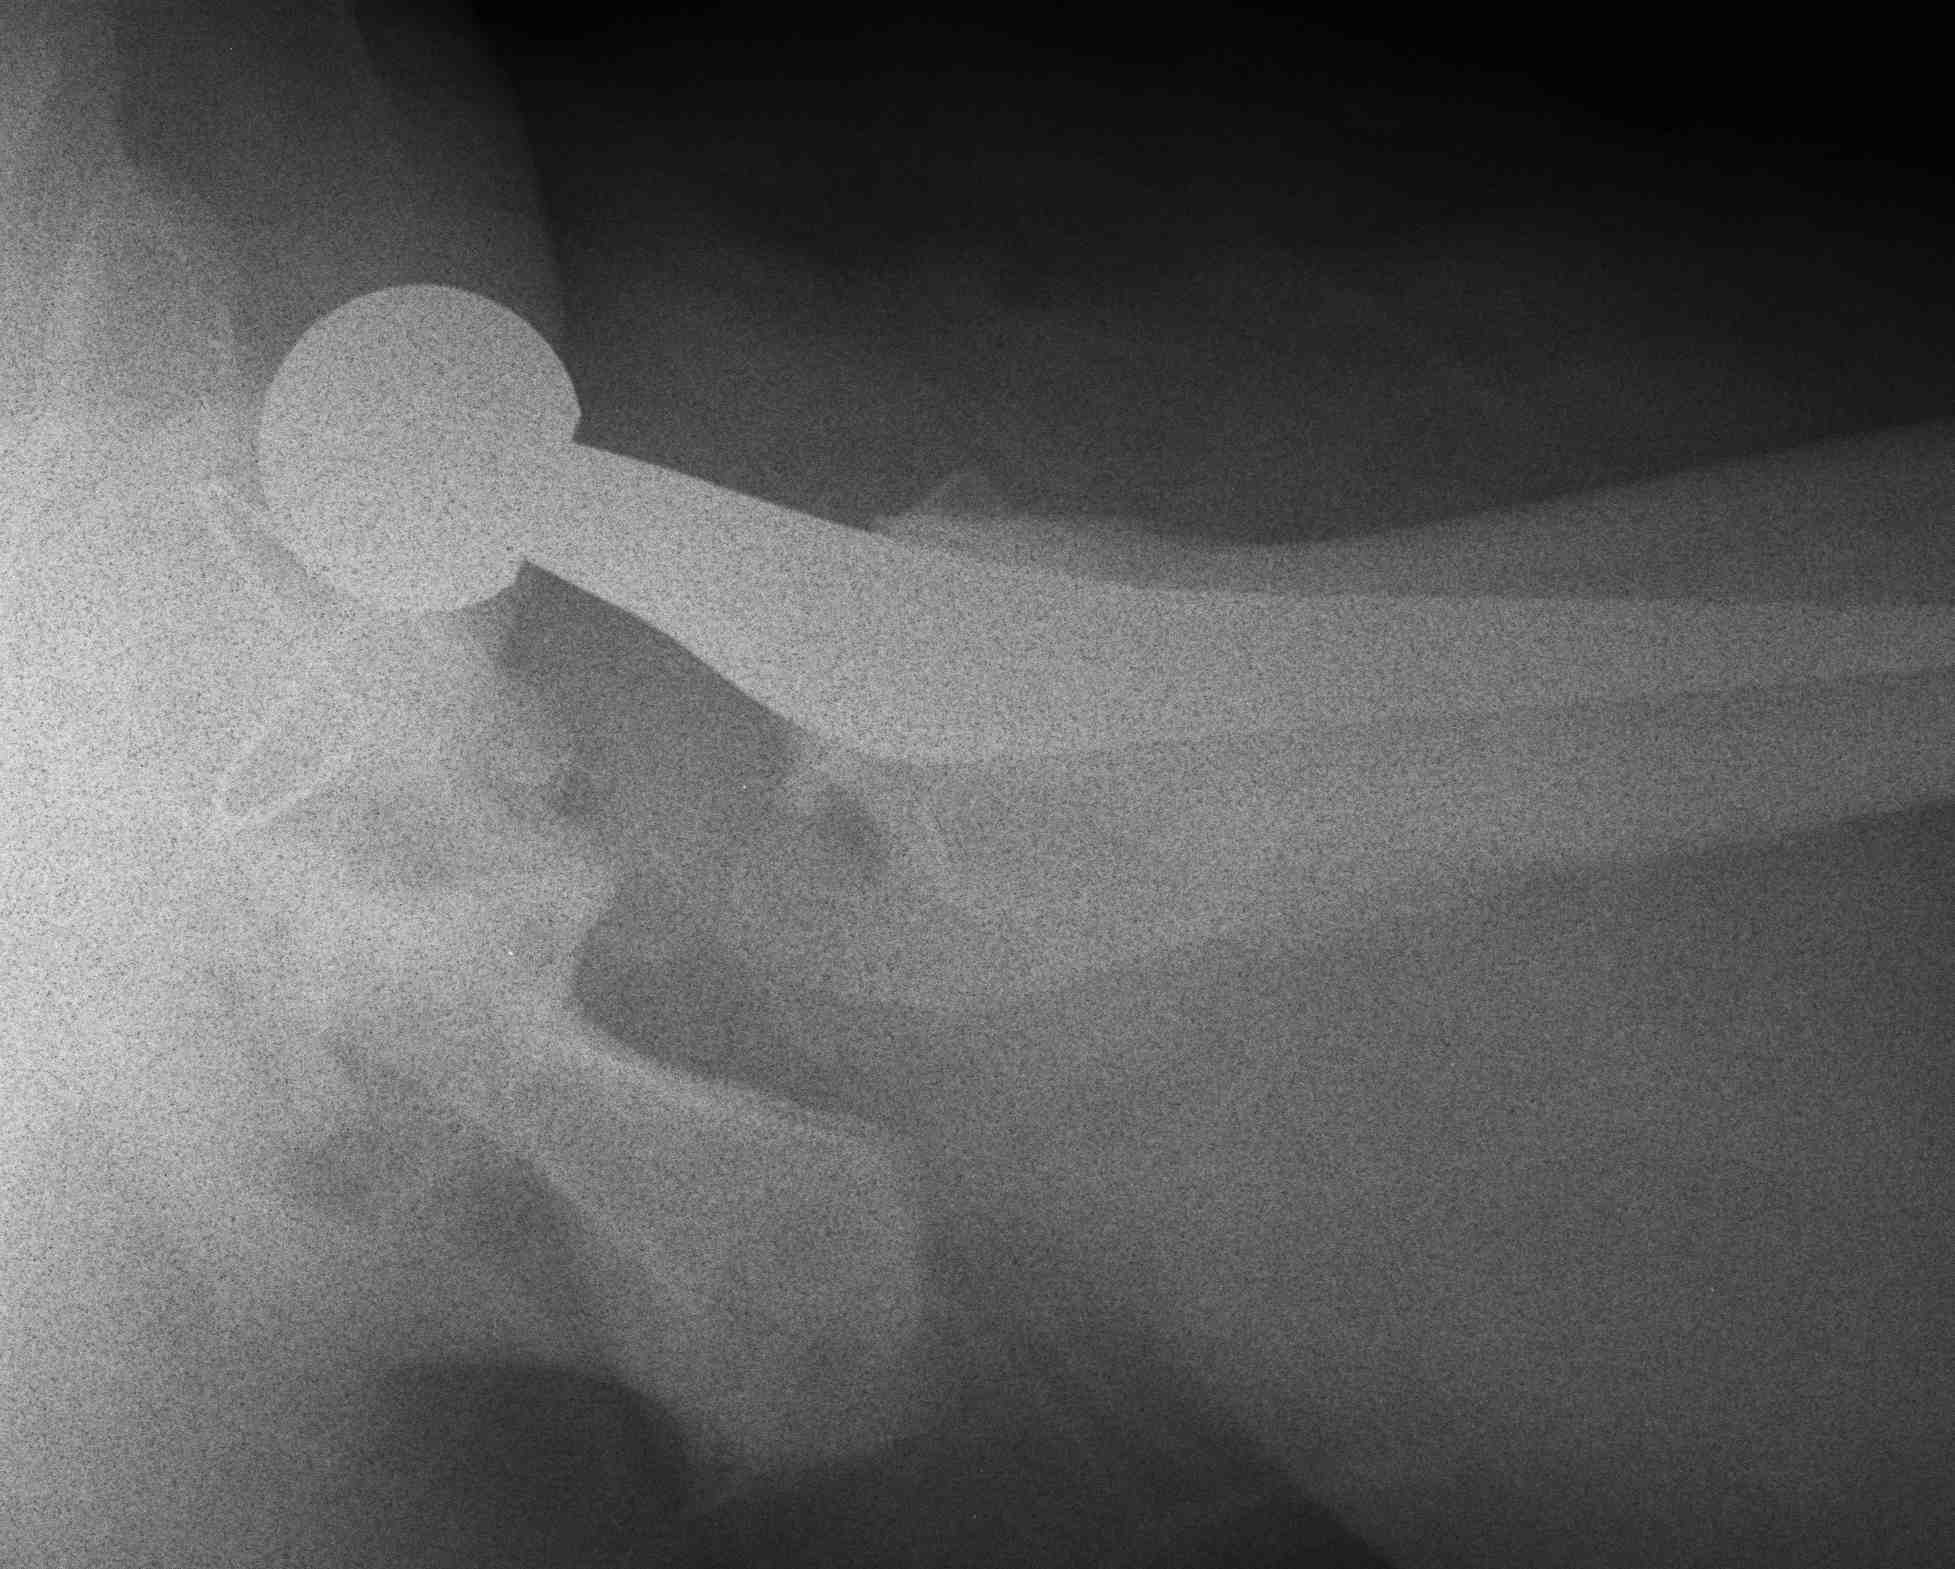

Anterior dislocation

- hip extended, adducted, externally rotation